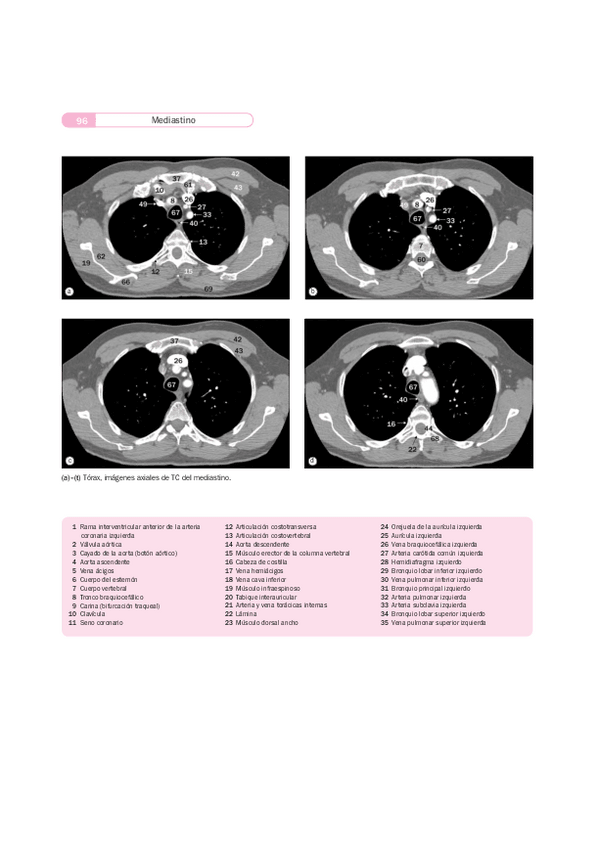

Apuntes - Imágenes radiológicas TAC RM.pdf

22 páginas